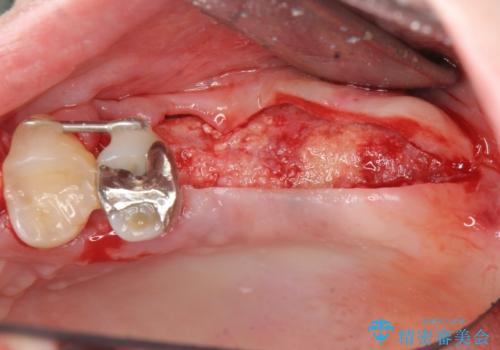

X線検査の結果、左上6には歯根破折、左上7には銀歯の下に大きな虫歯の再発が認められ共に抜歯をせずには症状の改善が見込めない状況です。

奥歯を2本失ったのち、しっかりと噛める環境へと整備するため、しっかりと骨の造成を行い清掃性を高めたインプラント治療を行っていくこととしました。

インプラントの仕上がりを見越して、ただ埋入するだけではなく長期的な予後を見込むには清掃のしやすい環境を整備することが大切です。

今回は大きく吸収してしまった歯槽骨をしっかりと造成することで、歯間ブラシを行いやすいインプラント周囲環境を整備することができました。